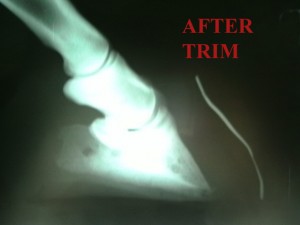

Below you can see the biomechanical effects of an Imprint trim. On the left you can see the excessive ‘dead’ toe left after the bone has rotated. The tip of the foot bone is pointing downwards at an alarming angle and you can almost imagine it crushing the sole. On the right, the heel has been brought down as far as possible, relieving some of the crushing effect. A lot of toe has been removed (although possibly a little more could come off) and you can see how much less leverage would be involved as the horse walks. This is a severe case of laminitis and demonstrates the effort that needs to be put in on such a case. This foot will need repeated trims and Imprint shoeings and you should not underestimate the commitment needed to fix one of these cases.